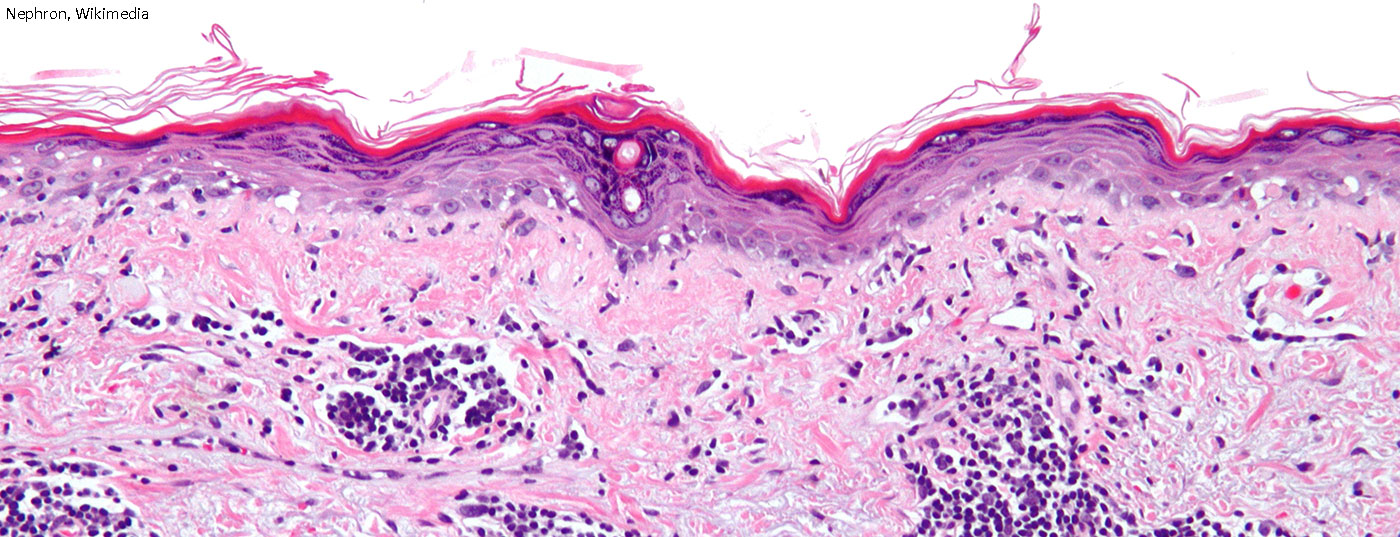

Die bisherigen Klassifikationskriterien für den Systemischen Lupus erythematodes (SLE) stammten im Kern aus dem Jahr 1982 und wurden lediglich 1997 geringfügig modifiziert. Höchste Zeit also, sich des Themas anzunehmen und den aktuellen Forschungsstand sowie neue Erkenntnisse einfliessen zu lassen. Perspektivisch kann mit der Zulassung mehrerer neuer Wirkstoffe gerechnet werden.